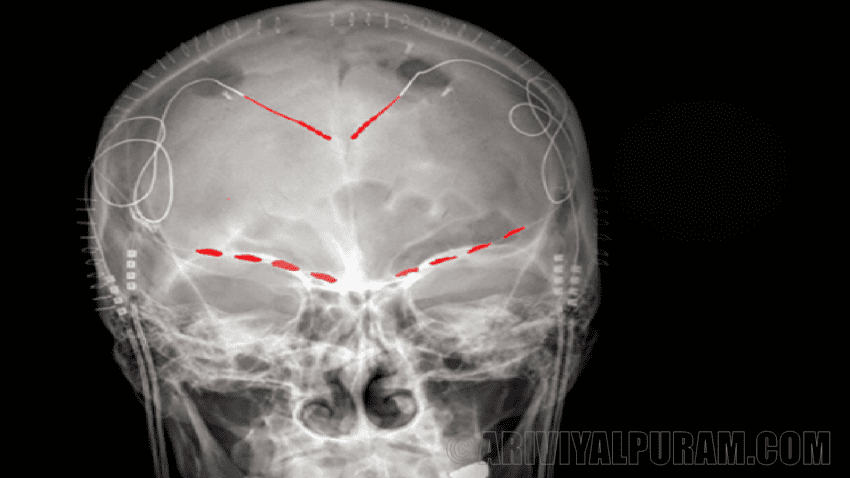

ஒரு சிகிச்சை அணுகுமுறை மூளையை மின்சாரம் மூலம் தூண்டுவதாகும். ஒரு மருத்துவ பரிசோதனையின் ஒரு பகுதியாக, கலிபோர்னியா பல்கலைக்கழக ஆராய்ச்சியாளர்கள், சான் பிரான்சிஸ்கோ நான்கு தன்னார்வலர்களின் மூளையில் நாள்பட்ட வலியுடன் நான்கு மின் கம்பிகளை பொருத்தினர். இந்த மின்முனைகள் இரண்டு மூளைப் பகுதிகளில் உள்ள நரம்பு செல்களை கண்காணித்து தூண்டலாம்.

ஆர்பிடோஃப்ரன்டல் கோர்டெக்ஸ், அல்லது ஓஎஃப்சி, மற்றும் முன்புற சிங்குலேட் கார்டெக்ஸ் அல்லது ஏசிசி. OFC மூளையில் ஒரு முக்கிய வலி செல்வாக்கு செலுத்துபவராக அறியப்படவில்லை, ஆனால் இந்த பகுதியில் ACC உட்பட வலி தொடர்பான பகுதிகளுக்கு நிறைய நரம்பியல் இணைப்புகள் உள்ளன. இது மக்கள் எவ்வாறு வலியை அனுபவிக்கிறது என்பதில் ஈடுபடுவதாக கருதப்படுகிறது.

ஆனால் ஆராய்ச்சியாளர்கள் மூளையைத் தூண்டுவதற்கு முன்பு, நாள்பட்ட வலி அதை எவ்வாறு பாதிக்கிறது என்பதை அவர்கள் அறிந்து கொள்ள வேண்டும். சுமார் 3 முதல் 6 மாதங்களுக்கு, பொருத்தப்பட்ட மின்முனைகள் இந்த நபர்களின் மூளை சமிக்ஞைகளை அவர்கள் தங்கள் வாழ்க்கையைப் பற்றிக் கண்காணித்தன. அந்த நேரத்தில், பங்கேற்பாளர்கள் ஒரு நாளைக்கு இரண்டு முதல் எட்டு முறை நிலையான அளவுகளில் தங்கள் வலியை மதிப்பிட்டனர்.

அதிநவீன இயந்திர கற்றல் அணுகுமுறைகளைப் பயன்படுத்தி, ஆராய்ச்சியாளர்கள் ஒவ்வொரு நபரின் வலி மதிப்பீடுகளையும் அவர்களின் மூளை செயல்பாட்டு முறைகளுடன் இணைத்தனர். இறுதியில் ஒவ்வொரு நபரின் நாள்பட்ட வலியின் கையொப்பத்தில் இறங்குகின்றனர். பல வழிகளில், வடிவங்கள் ஒவ்வொரு நபருக்கும் தனிப்பட்டவை, ஆனால் ஒன்றுடன் ஒன்று இருந்தது.

OFC இல் மூளை செயல்பாடு, கண்களுக்குப் பின்னால் மூளையின் முன்புறம், மக்களின் நாள்பட்ட வலி அளவுகளைக் கண்காணிக்கும். சில எதிர்பாராத வலி வடிவங்களும் வழியில் வளர்ந்தன. இரண்டு தன்னார்வலர்களின் வலி தோராயமாக மூன்று நாள் சுழற்சியில் ஏற்ற இறக்கமாக இருந்தது. ஓஎஃப்சியில் மூளையின் செயல்பாடு நாள்பட்ட வலியின் உறுதியான பயோமார்க்ஸைக் குறிக்கும்.